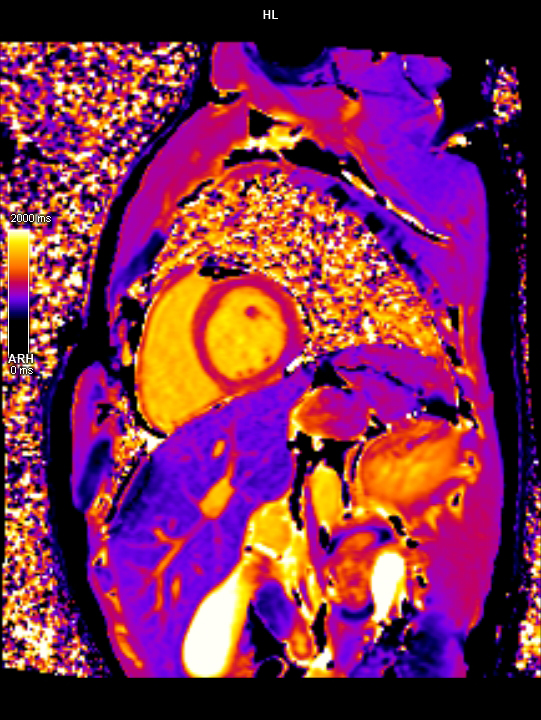

3 Tesla MR Çekim Görüntüleri

• 3 Tesla MR Çekim Görüntüleri